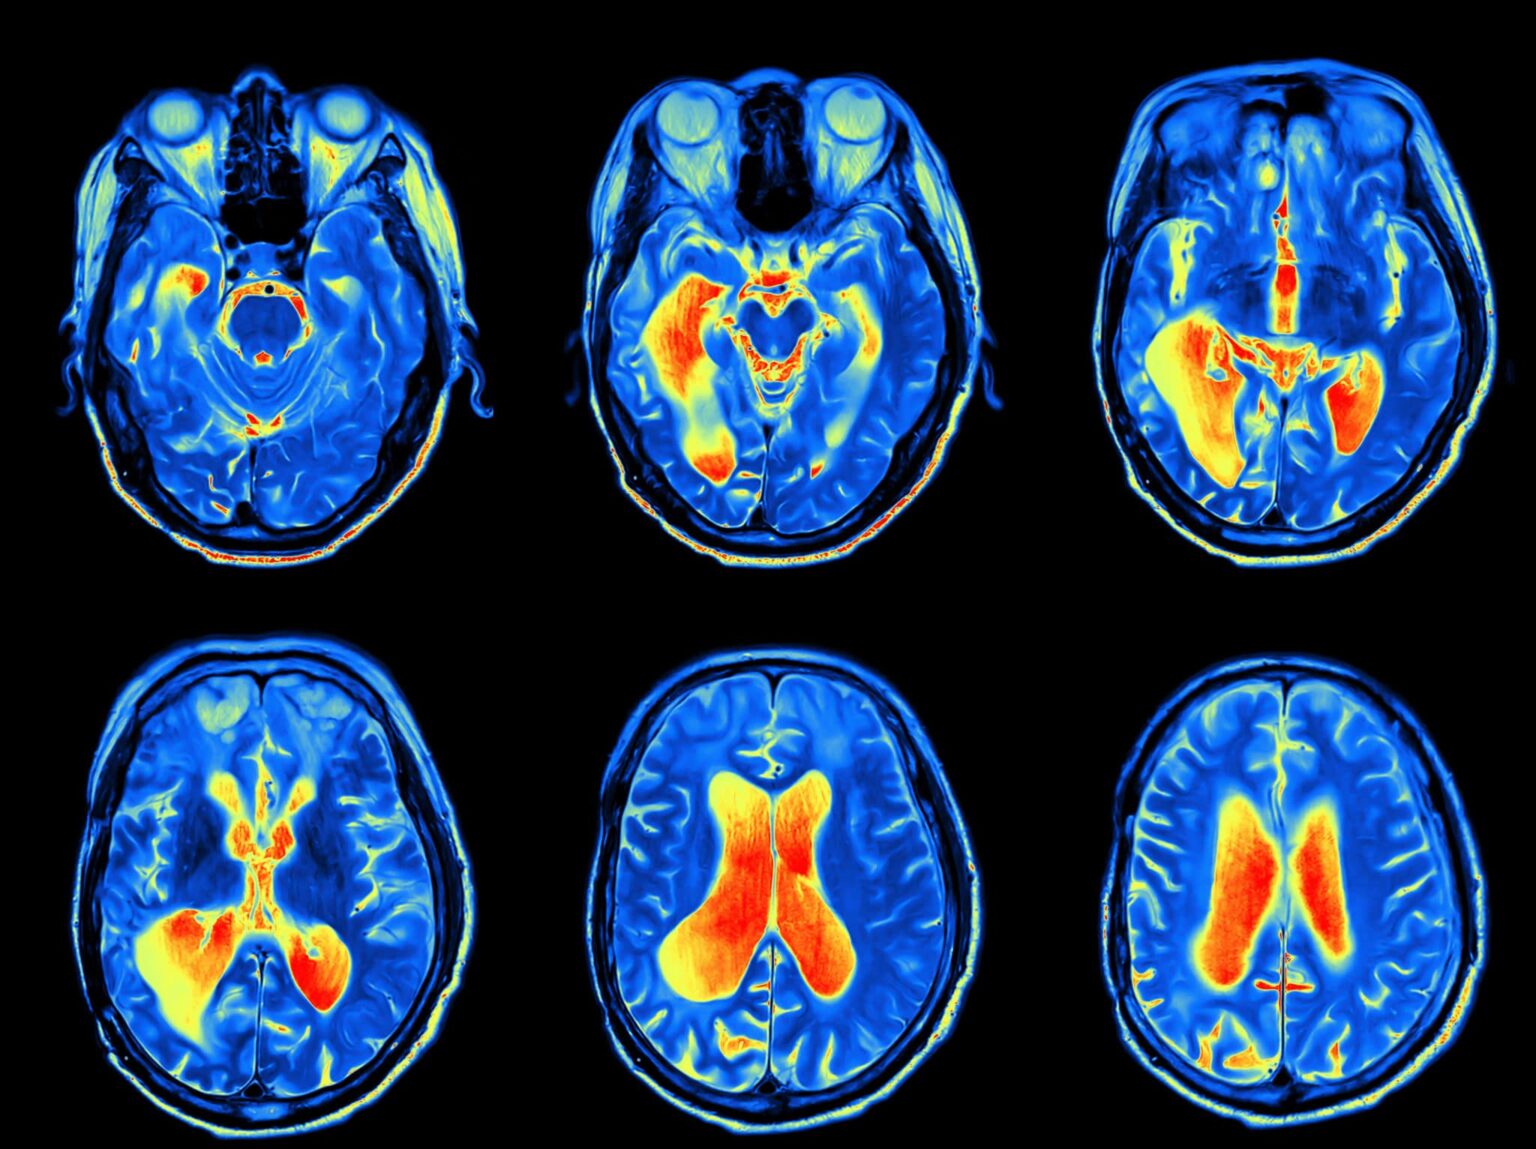

A series of MRI images of the brain during a skull base tumor exam.

Our otolaryngologist will begin by discussing your symptoms and their impact on your daily life and performing physical and neurological examinations. They may also perform a CT scan, MRI, bone scan and positron emission tomography (PET) scan.